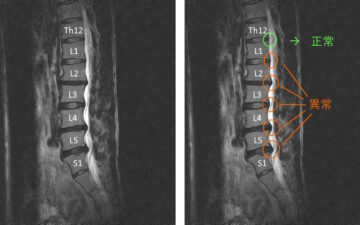

2回目の施術日の前日に整形外科でMRI撮影。かなりひどい腰椎椎間板ヘルニアであることが分かった。

画像を確認したところ、かなり重度の腰椎椎間板ヘルニアが認められました。

緑の〇の部分が正常な状態です。

赤〇の箇所は、椎間板が後方に飛び出ており神経を圧迫している様子がよくわかります。